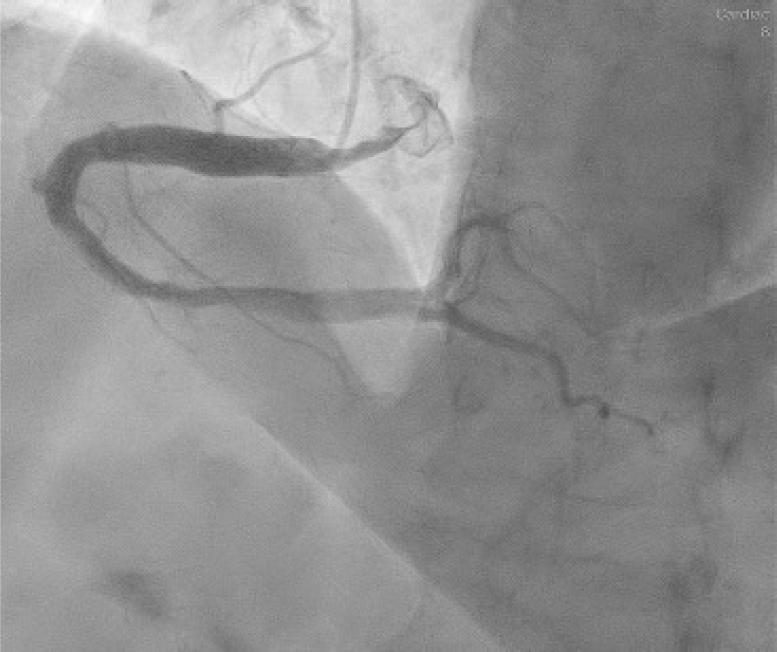

Left main coronary artery (LMCA) was also ectatic (maximum diameter of 10.3 mm in the mid-distal segment), as well as the left anterior descending (LAD) and left circumflex (LCx) arteries (with maximum diameters of 7.4 mm and 8.5 mm, respectively) (Figs. 3–4). Slow coronary flow was present in all vessels.

Caudal left anterior oblique projection of the left coronary artery. “Spyder” projection shows ectasia of the left main coronary artery (maximum diameter of 10.3 mm in the mid-distal portion) and left circumflex (maximum diameter of 8.5 mm in the proximity of the ostium).